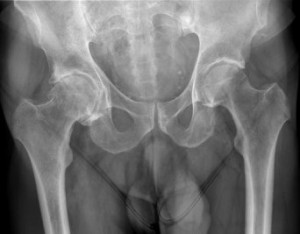

L’arthrose (ou coxarthrose) est l’usure du cartilage de votre hanche. Le cartilage est le revêtement protecteur qui permet aux os de glisser parfaitement l’un sur l’autre, comme un coussinet.

Avec le temps, ce cartilage s’abîme, s’affine et finit par disparaître. Les os se retrouvent alors en contact direct « os contre os ». Ce frottement crée de l’inflammation et devient très douloureux.

Si l’arthrose est souvent liée au vieillissement naturel, elle peut être accélérée par plusieurs facteurs :